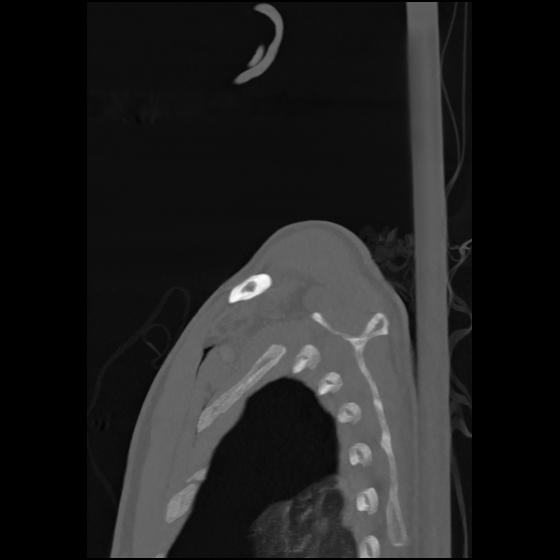

24 ANGIO,CE,Sag-MIP,5.000,ANGIO,Sag-MIP,